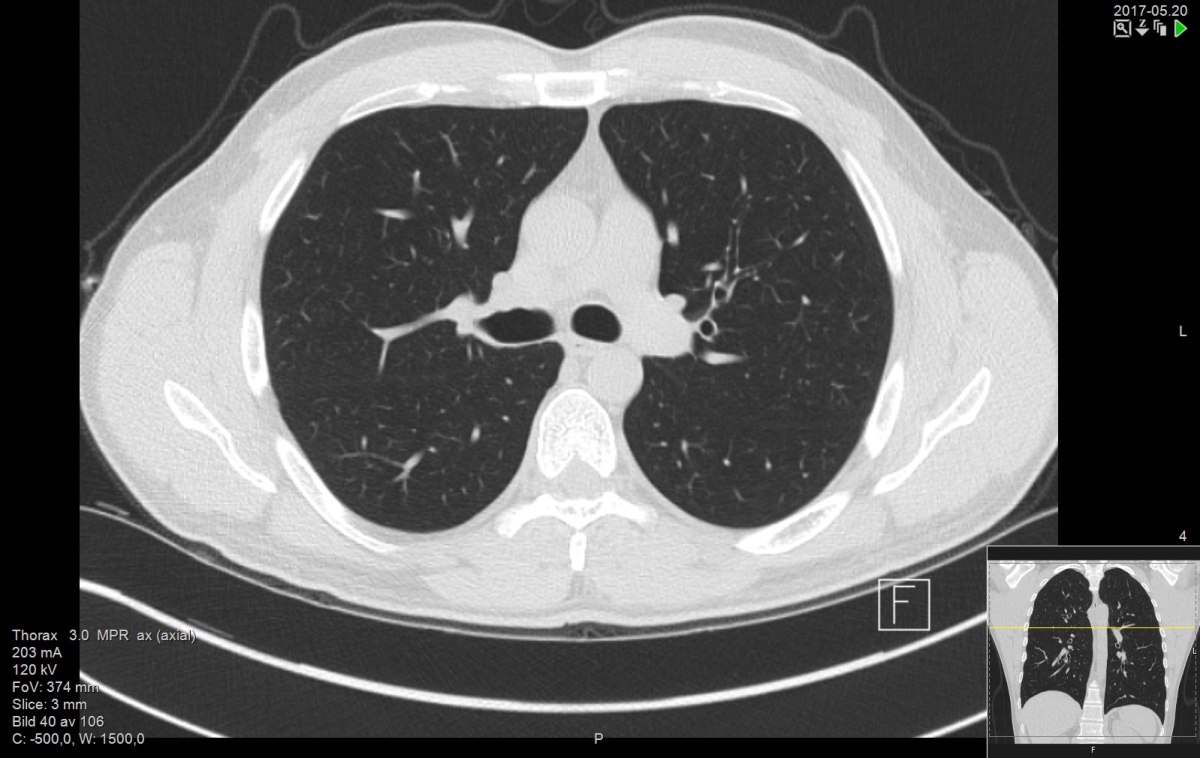

Τομογραφία θώρακος υψηλής ανάλυσης